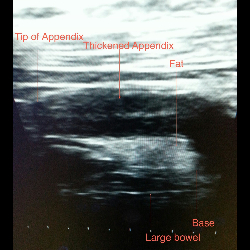

Appendicitis

Appendicitis

Appendicitis

Appendicitis